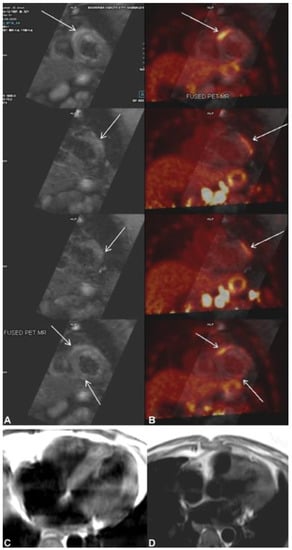

7. Role of Cardiac 18F-FDG PET

Recently, cardiac TB was diagnosed using 18F-FDG PET. In one of their case reports, Sundaraiya et al. presented a case of cardiac tuberculosis that resembled sarcoidosis [61]. PET imaging revealed patchy regions of increased FDG uptake in the apical to mid anterolateral, mid to basal anteroseptal/right ventricular, and moderately increased FDG uptake in the apical inferior LV myocardium CMR findings (Figure 7, This image was adapted from Sundaraiya et al. [61]). On whole-body PET CT imaging, several hypermetabolic supra and infra diaphragmatic lymphadenopathy was detected, but no pulmonary lesion was detected. Inflammation of the necrotizing granulomatous type in the left para-aortic lymph node was consistent with tuberculosis [61]. Even though tuberculosis closely resembles sarcoidosis, FDG-PET is helpful. FDG-PET has several drawbacks compared to CMR, including non-inflammatory myocardial FDG uptake despite good FDG-PET scan preparation, false-positive results due to atrial fibrillation, or bundle branch block, which can affect regional glucose utilization, and radiation exposure [62].

Figure 7.

(A) Cardiac magnetic resonance (CMR) shows multifocal subepicardial to mid-myocardial linear enhancement along the right ventricular insertion site, mid-anterolateral, and inferior segments (arrows) with corresponding focal myocardial edema. (B) Fused cardiac positron emission tomography CMR shows patchy areas of increased 18F-flurodeoxyglycose (FDG) uptake in the apical to mid-anterolateral, mid-to-basal anteroseptal at the right ventricular insertion site, and mildly increased FDG uptake in the apical inferior segments of the left ventricular myocardium corresponding to the regions of myocardial enhancement seen on CMR. (C,D) T2 black blood image showing T2 hyperintense changes in the left ventricular myocardium. The image was adapted from [61].